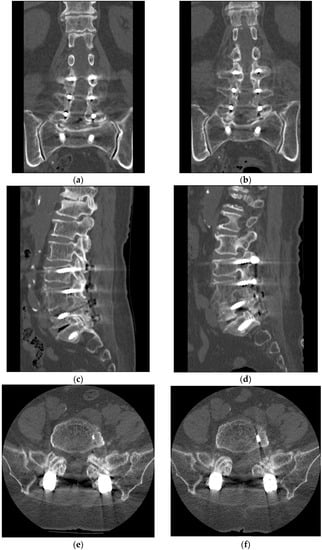

- Concordant imaging evidence of monosegmental FS at the same level within the fusion segment demonstrated on lumbar magnetic resonance imaging (MRI) and/or computer tomography (CT) scans;

2.2. Preoperative Work-Up

3. Results